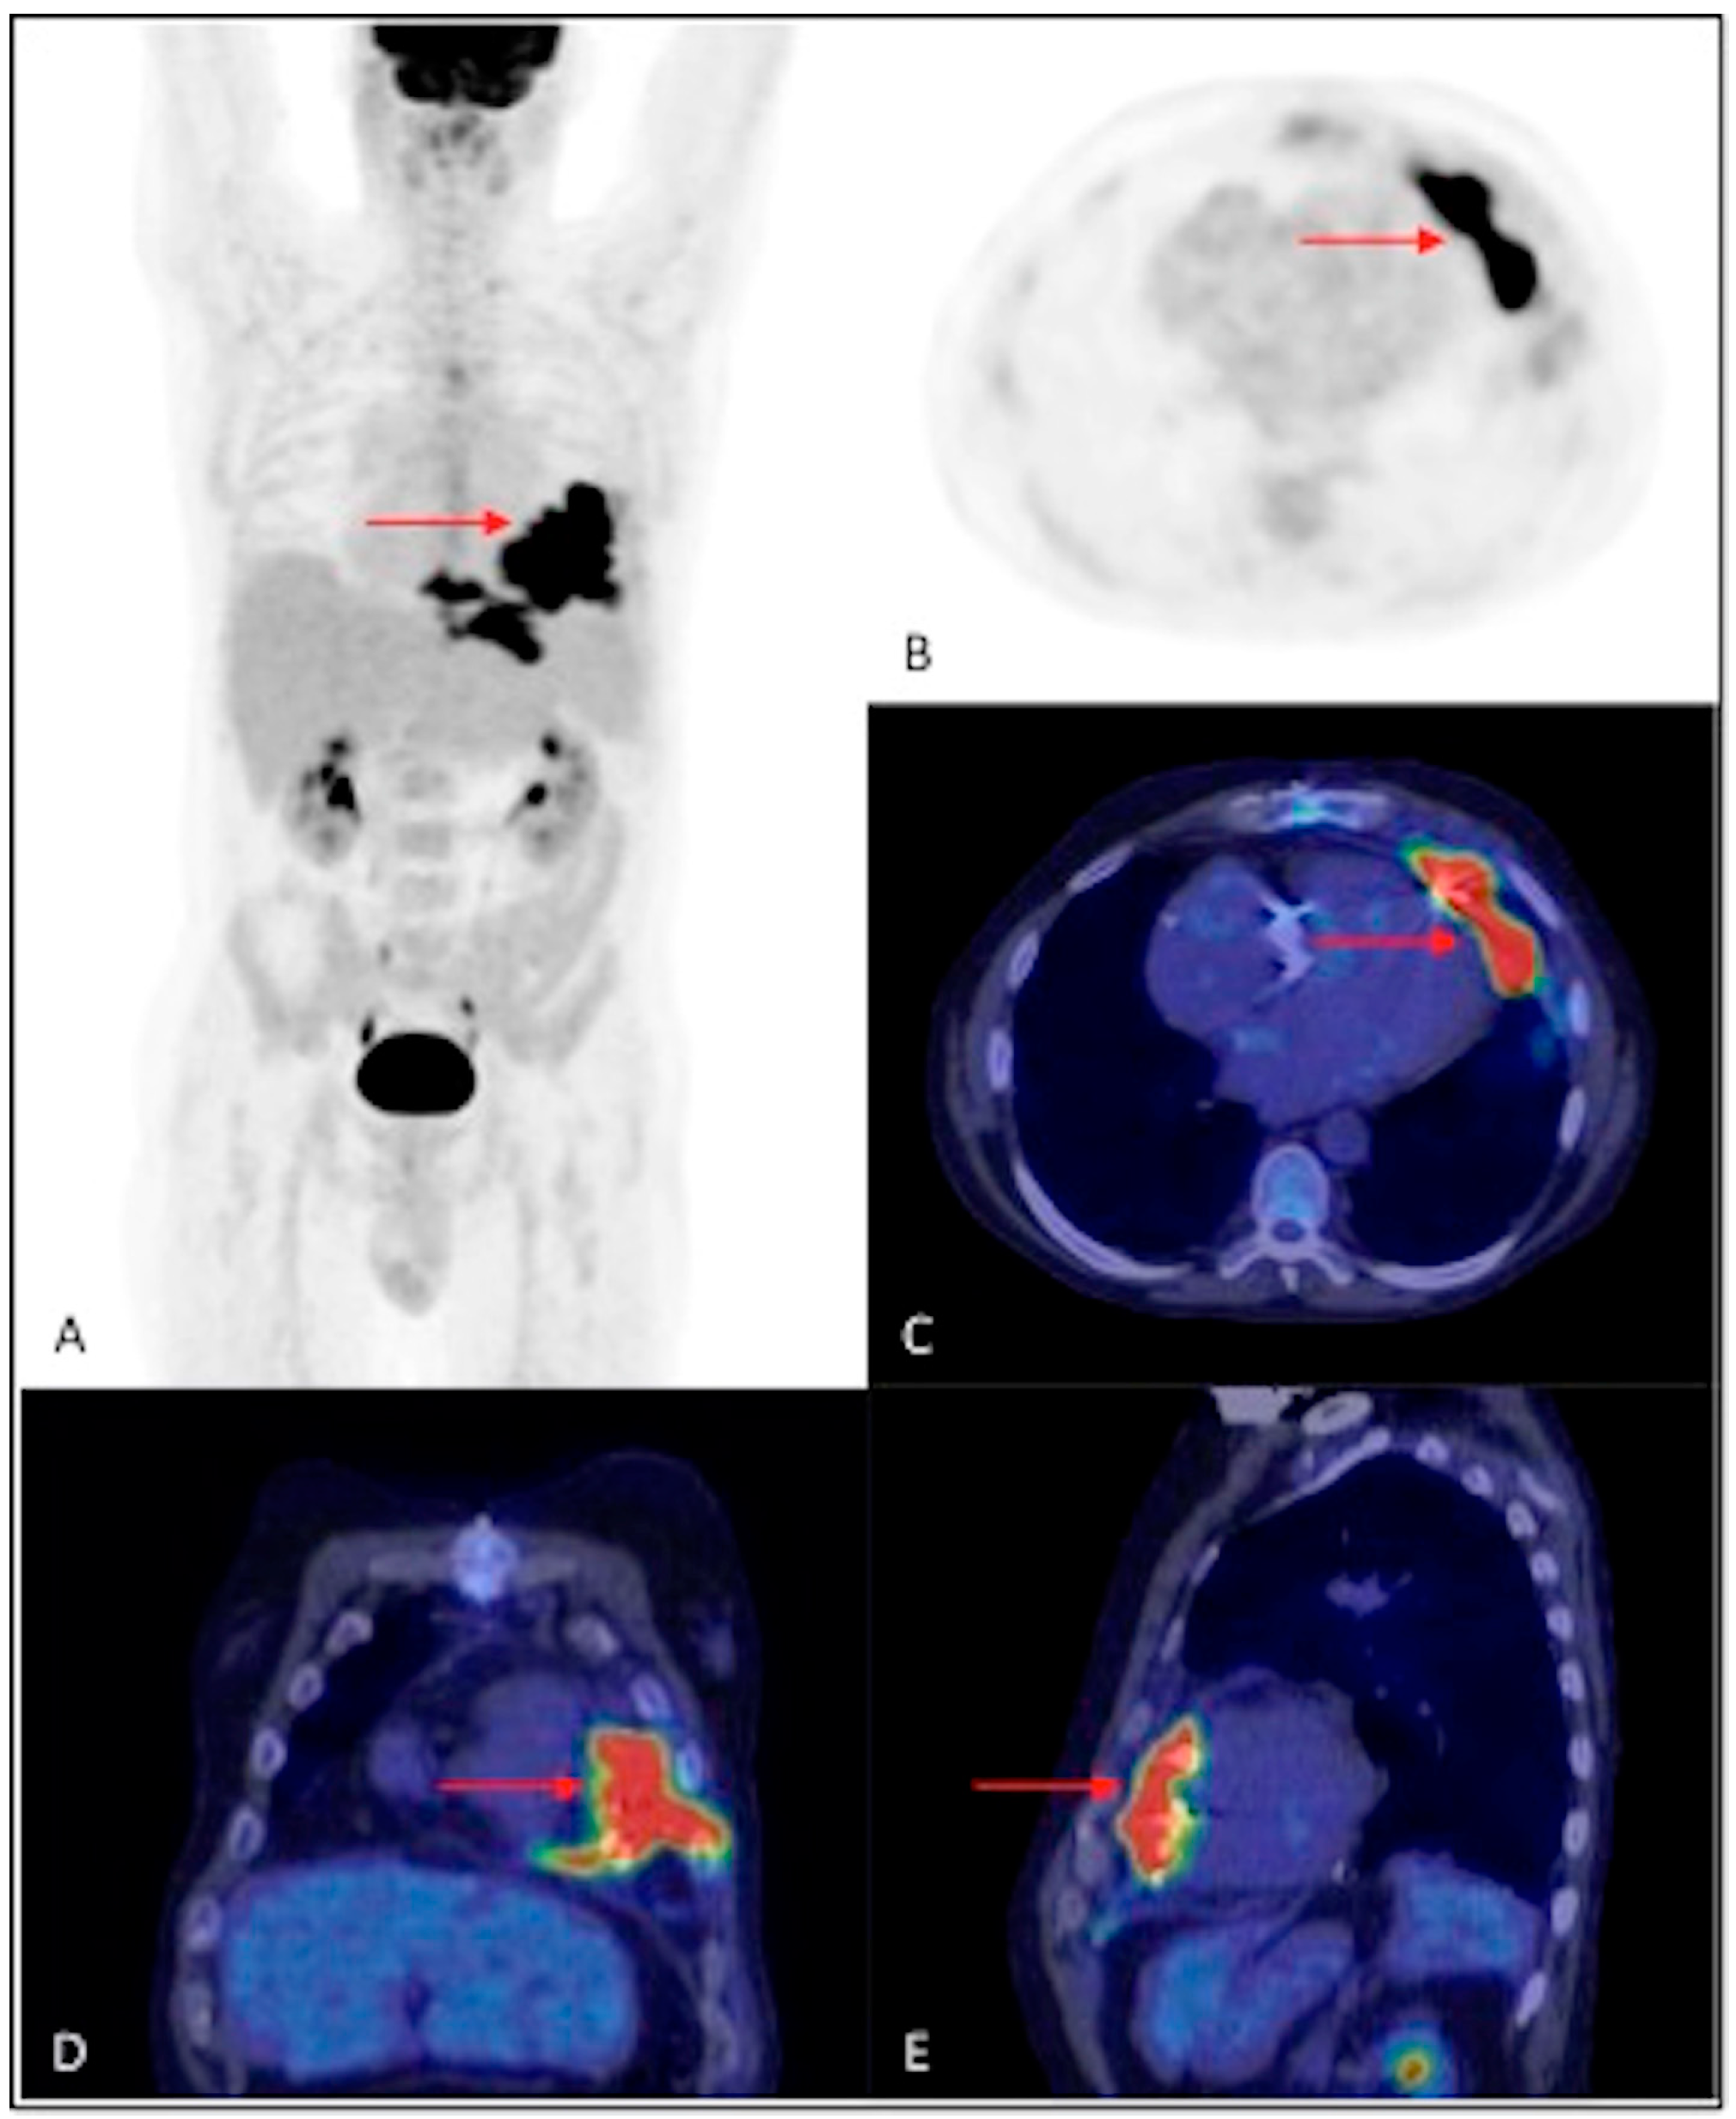

3.2. Results of the 18F-FDG PET/CT Examination Analysis